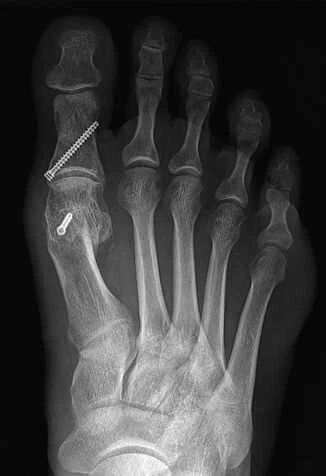

Operaci lze provádět otevřeným přístupem anebo modernějším zavřeným přístupem pod kontrolou rentgenu. [2 ] Níže fotografie nohy téže pacientky před a po zákroku: